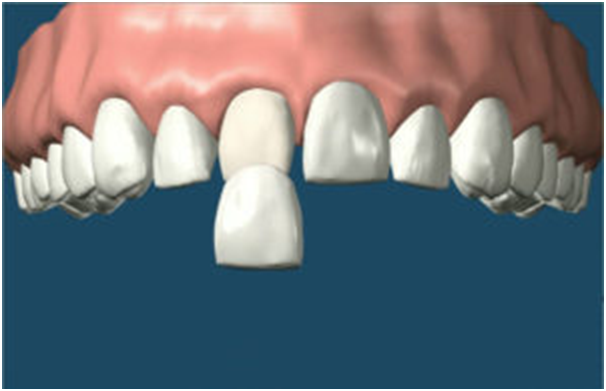

4. Crowns

If the tooth is extensively broken then a crown may be needed. A crown can be made of a variety of materials e.g. metal alloys or gold for the back teeth and ceramic for the front teeth. A crown restores the shape of the tooth above the gum i.e. the natural crown of the tooth, hence the name.

Note that if the injury to the tooth extends to the pulp or nerve of the tooth, then root canal treatment will be needed before the crown can be constructed. Crowns can cost depending on the material and difficulty involved.

Crowns can last for 10 years or more, with good care. If the tooth has sustained a vertical fracture or a crack that extends into the root, restoring the tooth may not be possible.